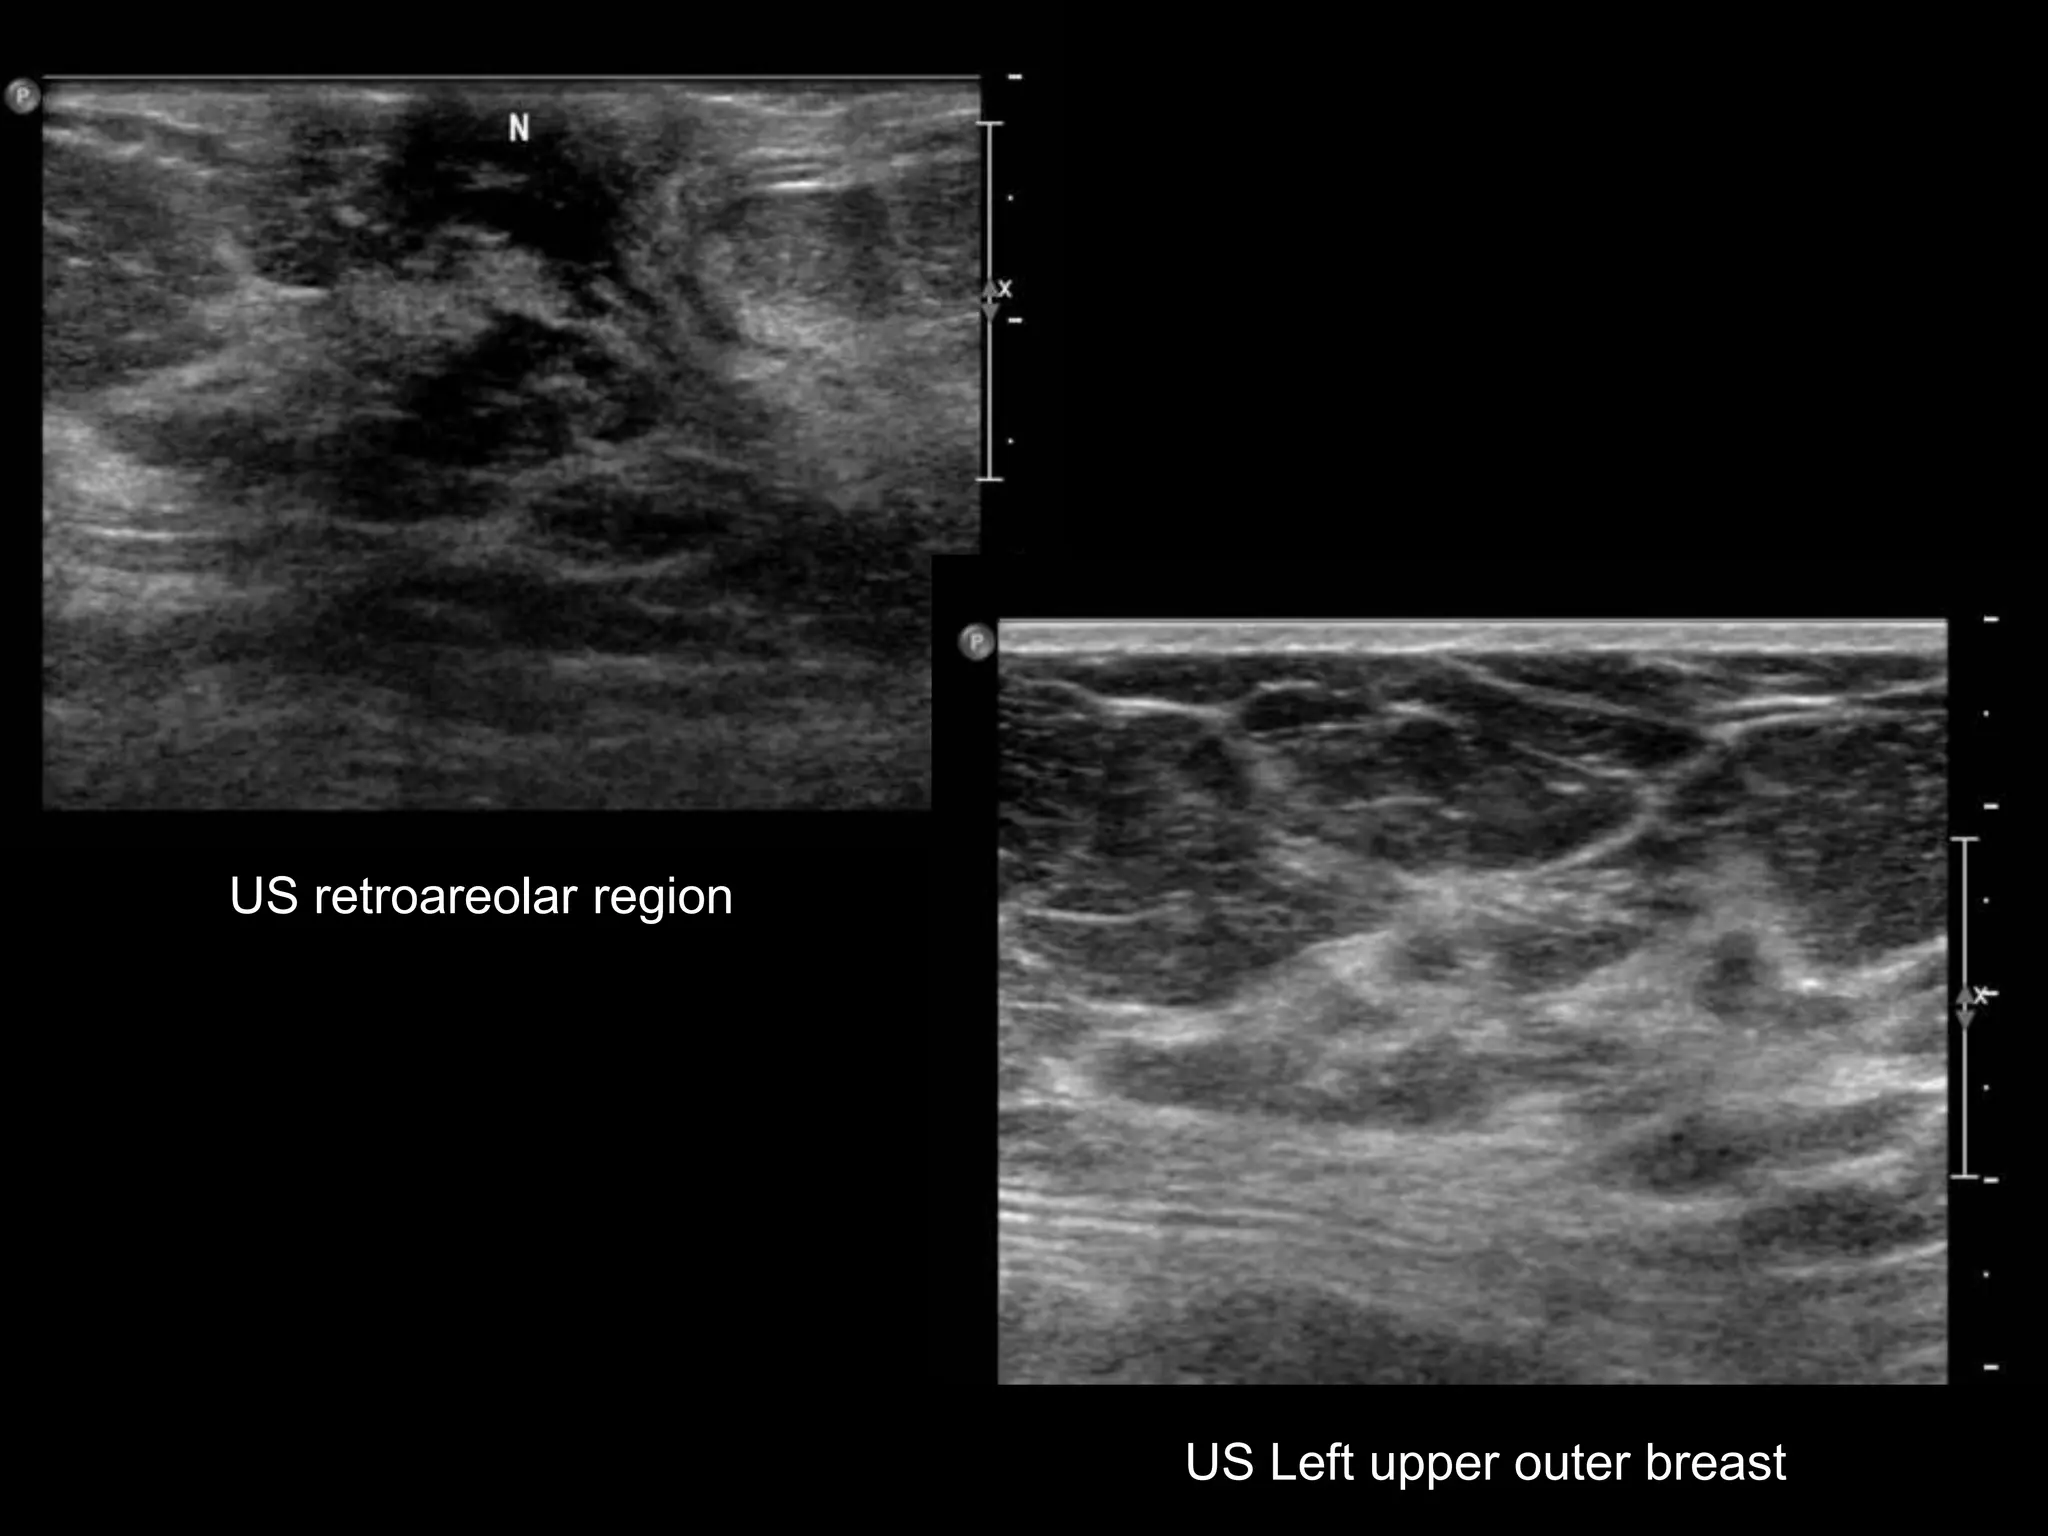

US retroareolar region

US Left upper outer breast

HISTORY

โ€ข 65 yo female

โ€ข Presents from OSH with worsening โ€žleft

breast swellingโ€Ÿ for 8-9 months

โ€ข New 1 month history of โ€žchange in left

nippleโ€Ÿ

Grade 2 Invasive Lobular Carcinoma

with LN positive for Metastatic Adenocarcinoma

SURGERY โ€“ Mastectomy with LN dissection

Invasive Lobular Carcinoma

โ€ข 10-15% of all invasive breast ca

โ€ข Sensitivity of MG 57-81%

โ€“ Mass most common โ€“ usually spiculated (44-

65%)

โ€“ Distortion 10-34%

โ€“ Asymmetry 1-14%

โ€ข Much less freq assoc with calcs than IDC

โ€ข Sensitivity of US 68-98%

โ€“ Spiculated mass

โ€“ Shadowing

Lopez et al. Radiographics 2009; 29:165.